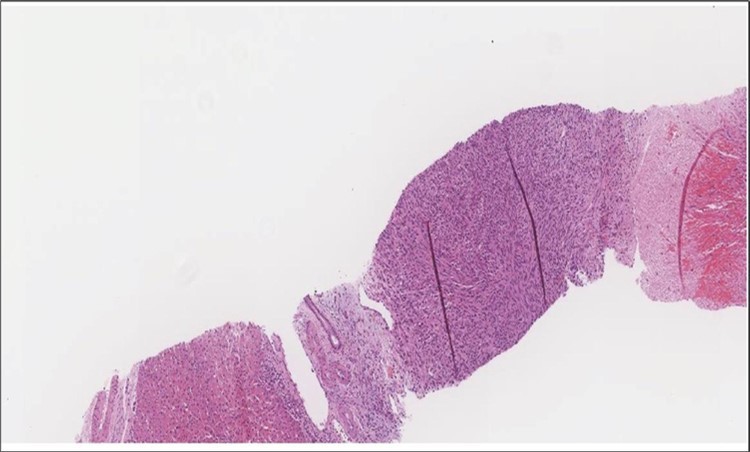

When diagnosing thyroid swelling, imaging studies have been helpful in differentiating malignant from benign tumors with US being used as an initial evaluation tool when assessing thyroid nodules. Tumors are categorized based on composition, echogenicity, shape, margin and echogenic foci into added scores determined by the TI-RADS system, which determines the need for FNA 13. Other imaging modalities include MRI and CT. However; radiological assessment does not distinguish between the types of thyroid cancer, and therefore FNA and biopsy are of crucial importance 3, 6. On a pathologic sample, LMS appears as spindled eosinophilic cells with elongated blunt-ended or cigar-like nuclei arranged in fascicles 2, 7 (Figure 1, Figure 2, Figure 3). Despite the unique microscopic morphology, LMS cannot be distinguished from other spindle cell tumors such as spindle cell variant of medullary thyroid cancer, anaplastic thyroid

Figure 2.Left thyroid On a Higher power, few thyroid follicles are noted and the lesion is composed of spindle cells with sweeping fascicles (H&E, ×200).

Figure 3.Left thyroid The malignant looking cells are showing diffuse atypia, mitosis and hyper-chromatic nuclei, some remaining follicles could be noted as well (H&E, ×400).

cancer, or other metastatic tumors without further testing with genetic or molecular studies 3, 7. Immunohistochemical testing plays a vital role in differentiating LMS from such similar tumors as it stains positive for vimentin and smooth muscle actin (SMA), and is variably positive for HHF35, desmin (50%-100%), and H-caldesmon 3, 6. Moreover, there were no reported cases where thyroid LMS stained positive for thyroglobulin, cytokeratin, calcitonin, chromogranin, or protein S100 3. Our patient’s left thyroid biopsy showed the characteristic microscopic features and was positive for SMA, desmin, caldesmon, P63 with patchy EMA (Figure 1, Figure 2, Figure 3, Figure 4) as well as her liver biopsy (Figure 5, Figure 6, Figure 7); whereas her right thyroid showed clear papillary thyroid cancer cell features (Figure 8, Figure 9).